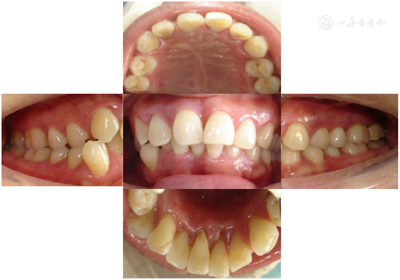

全口临床检查:口腔卫生状况一般,菌斑、软垢少量,下前牙舌侧可见新生牙石,龈下牙石(++)。牙龈色偏红,肿胀,形态圆钝,质软,尤以下前牙舌侧为重,出血指数3~4。全口牙齿探诊深度(PD)5~7 mm,个别位点8~9 mm。全口牙齿均可探及附着丧失,21、24、25、41、43松动I~Ⅱ。46合面金属色充填体,27烤瓷冠复体,近中悬突,可见食物嵌塞,叩痛(-)。咬合关系深覆合,下前牙多生牙,下前牙区拥挤,43位置颊倾,反合,见图1,图2,图3。